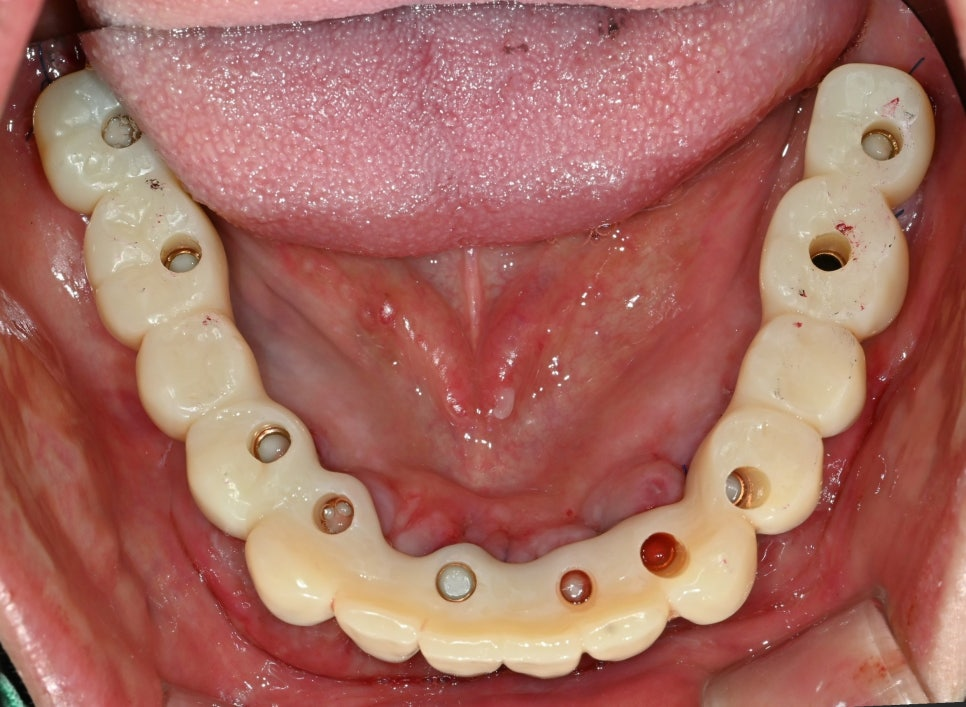

『골 유착 이후』

골 유착이 확인되어

충분히 고정되었습니다.

윗쪽은 틀니를 제거하고

보철을 사용하며 미리

적응하는 시간을 가졌습니다.

2024.12.11

이후 최종 보철이 장착된

사진입니다.

당일 기공 작업을 끝내

즉시 하중을 부하했습니다.

그렇기에 전체 임플란트

기간을 단축시킬 수 있었죠.